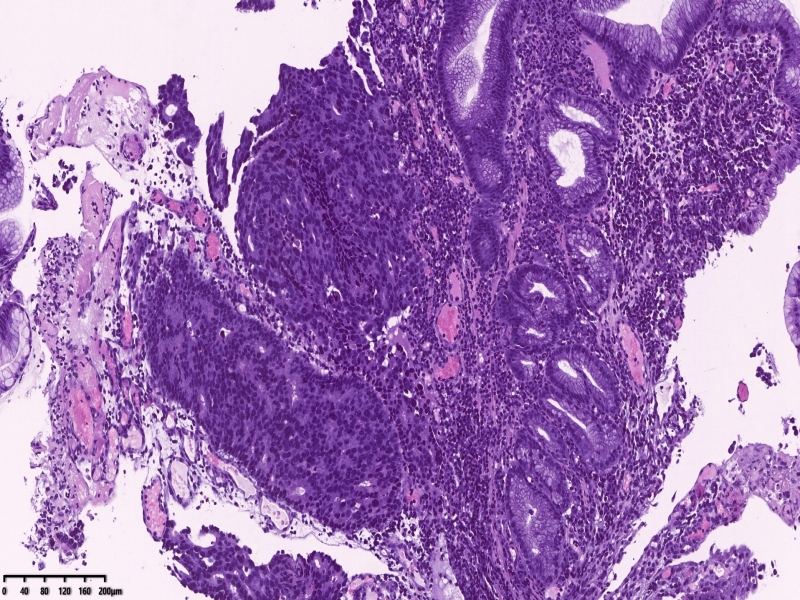

镜下所见:胃粘膜组织数块,炎症背景,其中3块固有层内可见细胞团,瘤细胞排列呈条索状迂回后呈巢状,巢的边缘瘤细胞呈栅栏状。细胞形态似柱状。

第一感觉考虑神经内分泌肿瘤?会诊考虑低分化腺癌。以前也遇到一个类似病例,贲门口占位,初步考虑神经内分泌肿瘤,但是神经内分泌标记均为阴性,最后考虑低分化腺癌。